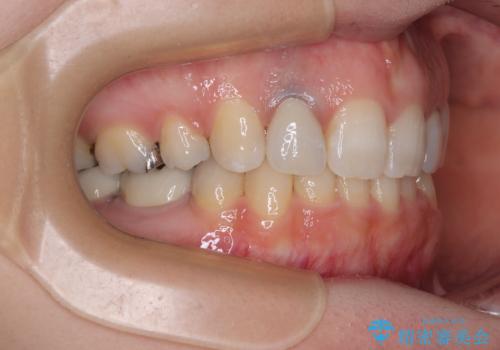

抜歯したスペースがなかなか閉じず、治療に時間はかかりましたが、術前術後のむし歯治療と合わせて3年10ヶ月で治療を終えることができました。

途中結婚により遠方に引っ越しをされたため、むし歯治療は取り急ぎ目立つところをセラミッククラウンとしましたが、今後落ち着いてきたら他の部分も行っていく予定です。